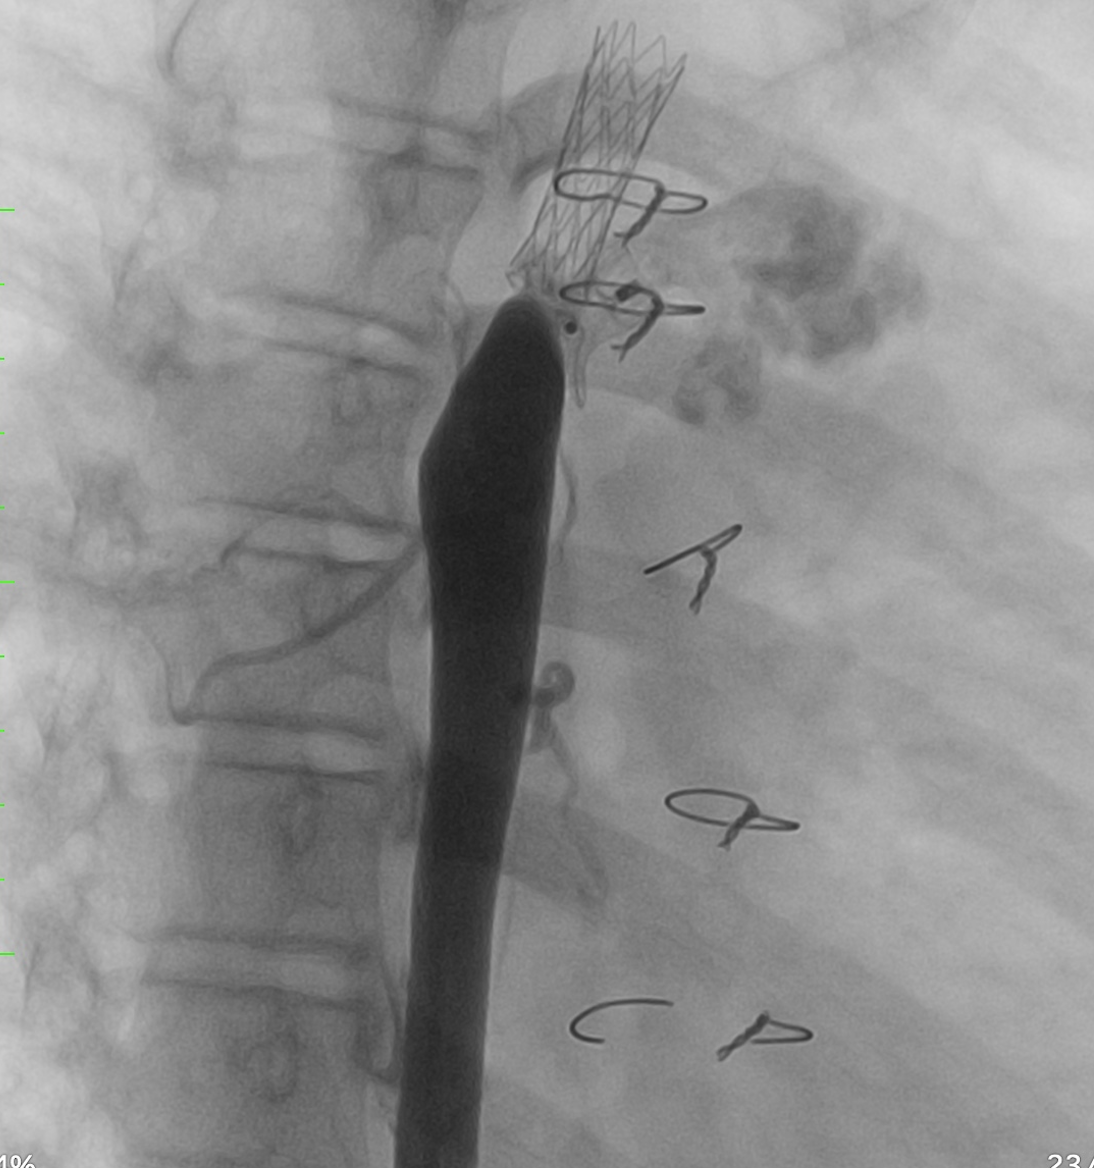

Echocardiography and CTA revealed severe stenosis in the distal part of the coarctation stent, caused by displacement of the PDA device. There was a residual shunt through the PDA measuring 3.5mm, with a slight left-to-right shunt. The narrowest diameter of the stent was 4mm. Additionally, a bidirectional shunt muscular outlet VSD with a diameter of 6mm was noted. The function of the left ventricle was preserved

Relevant Catheterization Findings

The aortography revealed severe stenosis in the distal part of the coarctation stent, caused by displacement of the PDA device, which had shifted toward the descending aorta. There was a residual shunt through the PDA with a slight left-to-right shunt. The diameters of the ascending aorta, aortic arch, and descending aorta were 22mm, 9mm, and 13mm, respectively. The narrowest diameter of the stent was 4mm.

Firstly, an angiography was performed to confirm the positions of the CoA stent and PDA device. A 0.014” microwire (Transcend, Boston Scientific) was used to cross through the PDA device to reach the upper part of the aorta. A 5F guiding catheter was advanced toward the proximal stent but was unsuccessful. To assist with advancing the 5F guiding catheter, we used a 3.0 mm and 5.0mm balloon to dilate the opening beside the PDA device. An angiography was then conducted to assess the relative positions of the CoA stent and PDA device. We decided to deploy an additional stent to cover the distal part of the previous stent to direct the PDA device towards the pulmonary artery. A 7F delivery system was advanced to the optimal position, and a 21L AndraStent was successfully deployed. A 8.0mm high-pressure balloon (VACS III) was then used to further dilate the stent. The pressures in the ascending and descending aorta (below the stent) were recorded as 115mmHg and 90mmHg, respectively. Finally, an angiography confirmed the correct positioning of both the stent and the PDA device without complications.